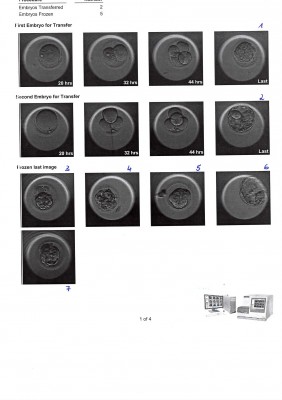

aus PICSI sind folgende im Bild zu sehende Embryonen an Tag 5 der Kultivation entstanden. Die zwei oberen wurden transferiert. 5 kryokonserviert.

Können Sie mir sagen ob das wirklich alles Blastozysten sind? Einige sehen, finde ich, eher wie Morulas aus. Zur Begründung wurde gesagt, dass die Embryonen pulsieren und es unmöglich ist alle gleichzeitig im vollen Bild zu fotografieren. Kann das sein?

Können Sie bitte auch was zur Qualität der Embryonen sagen? Das wurde uns nicht genau erläutert. Die beiden transferierten Embryonen sollen expandierende Blastozysten sein. Und der Rest?

An Hand der Bildern an d5 würde kann ich die Embryonenqualität so beschreiben:

Embryo 1: gute, gleichmäßige Strukturen, entweder eine kollabierte BC oder eine Morula

Embryo 2: schöne BC 2BB oder 3BB

Embryo 3: beginnende BC, mittlere Qual.

Embryo 4: beginnende BC, mittlere Qualität

Embryo 5: sehr schöner komp. Embryo, für Tag 5 nicht ganz zeitgerecht

Embryo 6: BC mit Expandierungsgrad 3 bis 4, mit einer schönen innerern Zellmasse, äußere Zellmasse etwas eingeschränkt

Embryo 7: beginnende BC, mittlere Qualität

Mit den beiden transferierten BCs haben sie sehr gute Chancen und ich wünsche

ihnen viel Glück mit den beiden.